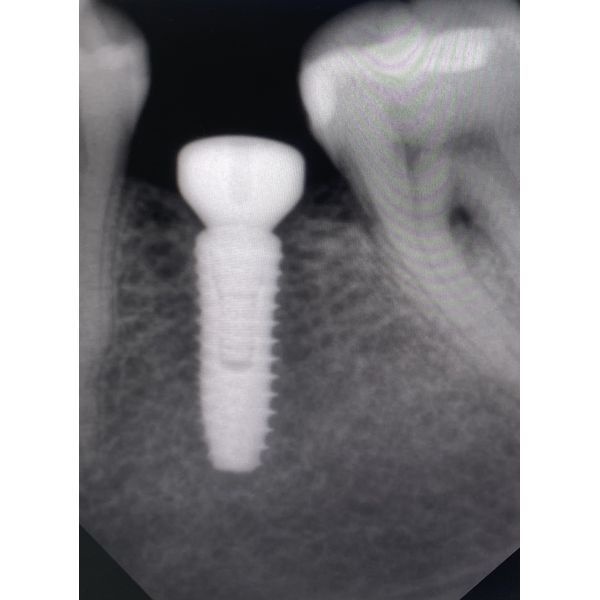

- установили дентальный имплантат и проверили его стабильность;

- провели рентген-контроль.